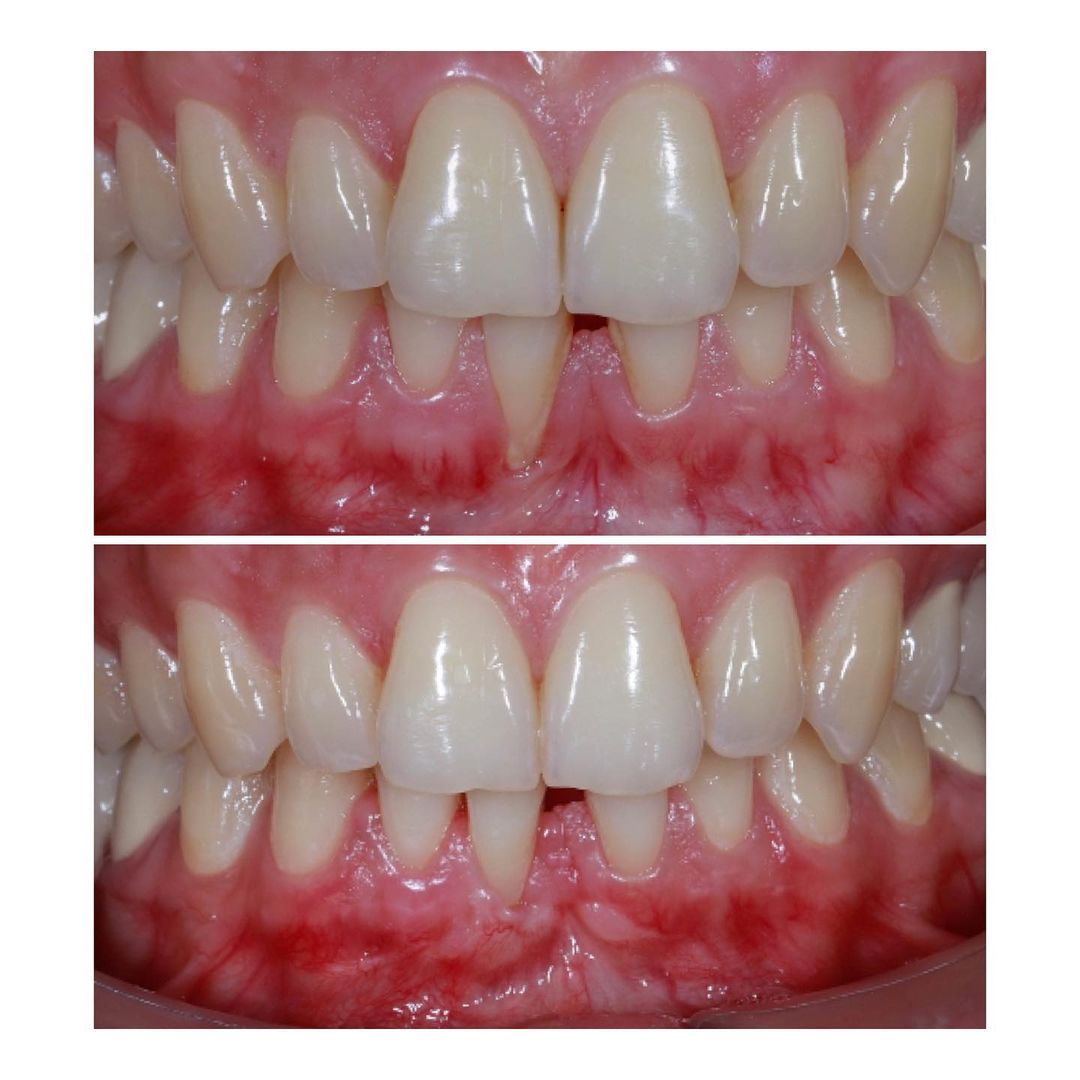

Alt kəsici dişətinin çəkilməsi olan pasientin damaqdan diş əti parçası alaraq bərpası